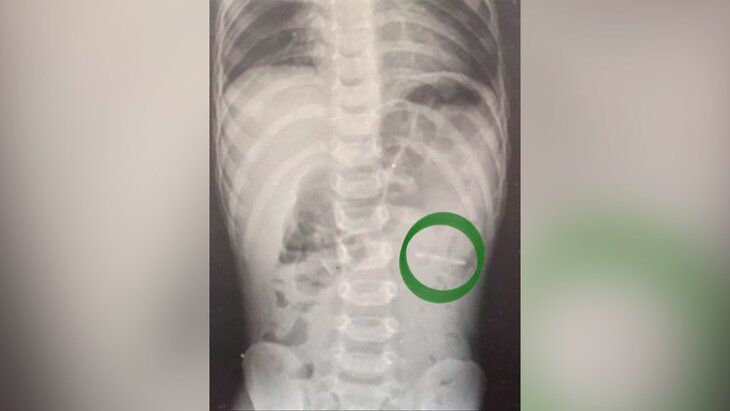

Врачи Раменской больницы спасли полуторагодовалого ребенка, который по неосторожности проглотил ключ от металлической банки. Об этом сообщает пресс-служба подмосковного Минздрава.

В больницу мальчика доставили родители. Ребенку сразу же сделали рентген органов брюшной полости, в результате которого было выявлено, что ключ находится в желудке. При этом слизистые оболочки внутренних органов не были повреждены.

Врачи вытащили ключ с помощью эндоскопического оборудования. В настоящее время мальчик чувствует себя хорошо и уже находится дома.